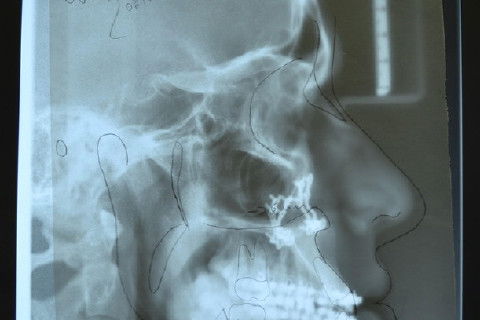

Telerradiografia de perfil pós-operatório sobreposto pelo traçado predictivo pré-operatório, nota-se boa correlação...